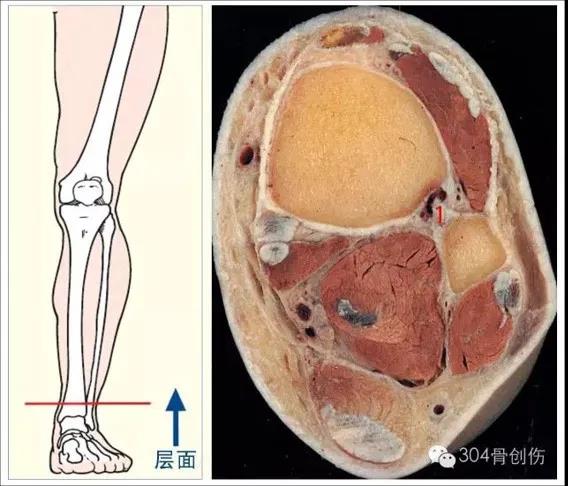

踝关节解剖

x线检查

CT检查

MRI检查